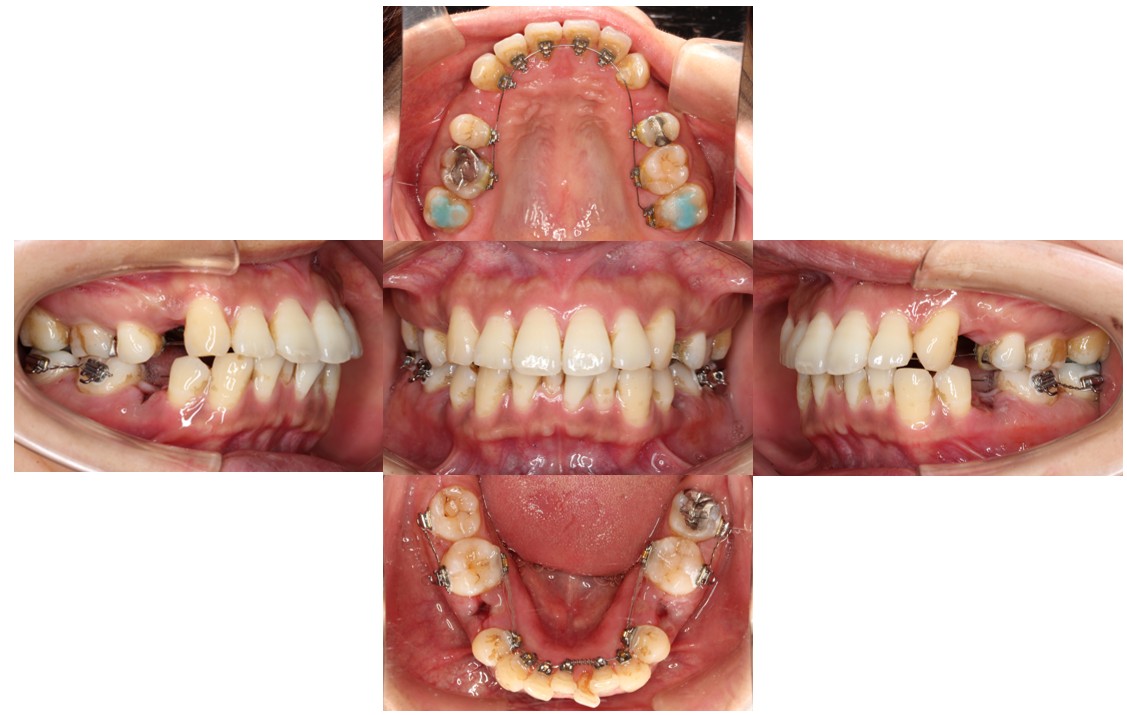

装置装着時の口腔内の状態です。

上顎左右4番目、下顎左右5番目の箇所を抜歯し、上下裏側(リンガル)の装置で動かしていきます。

現在の歯並びだと、下の歯が上の歯の装置にぶつかってしまう状態のため、下の奥歯にバイトアップという青い材料をつけて嚙み合わせをあげています。